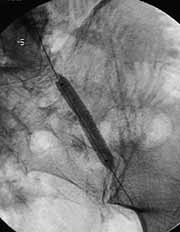

Увеличить

Рис. 5. Имплантация BY-STENT. Атеросклероз брюшной аорты и ее ветвей.